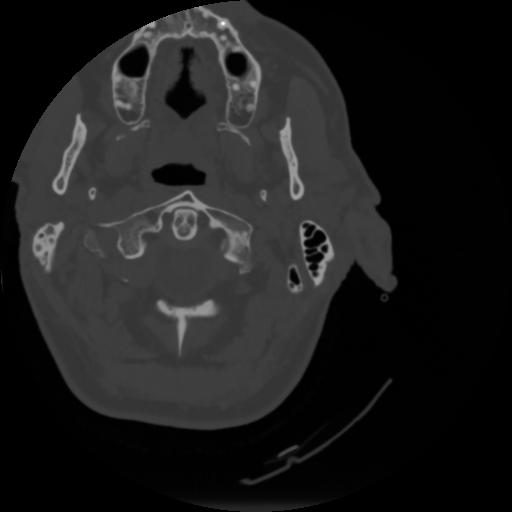

4 CEREBRO,,Vol,0.5,CEREBRO,,